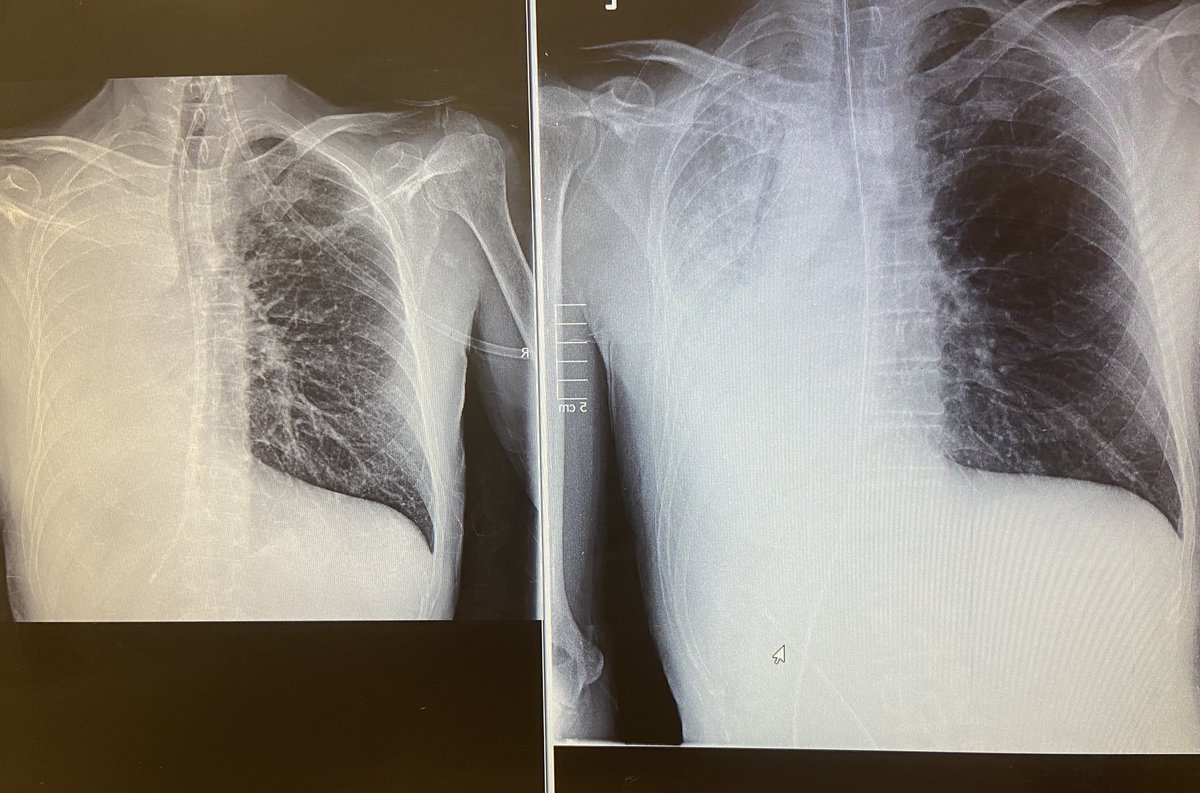

New appreciation for the cough assist today 😍 left X-ray is pre treatment with a complete white out, the right x-ray shows post treatment 😍 improved patient comfort, reduced o2 requirement and +++secretions cleared! #respisbest Great Western Hospitals NHS Foundation Trust Ceri Owen Andrew Hurden 🫁🩺💪🏻